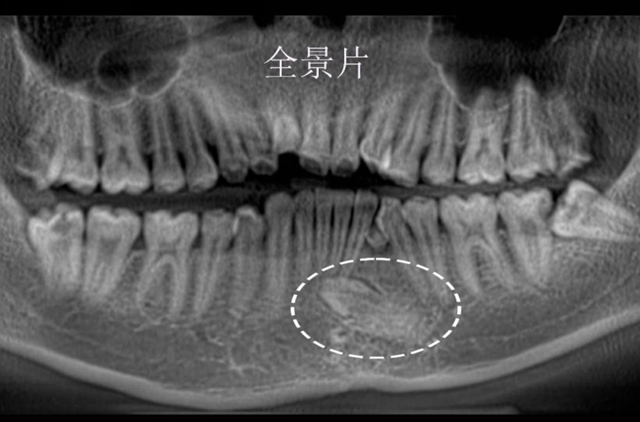

小陈最初就诊的原因很常见,牙齿排列不齐影响外观,咀嚼也受影响。本以为常规矫正就能解决,可口腔检查和X光片却查出了大问题。

彭培钊发现小陈左侧下颌尖牙是颗早该脱落的乳牙,正常应该长出来的恒牙尖牙反而“躲”在了下颌骨里,牙冠直对着下前牙的牙根,只有毫厘之差。

更棘手的是,这颗埋伏牙周围还绕着一支很少见的直径0.9mm血管,比常见的颌骨内血管粗不少。

通过数字化三维重建技术,精准定位埋伏牙与神经血管的位置关系。